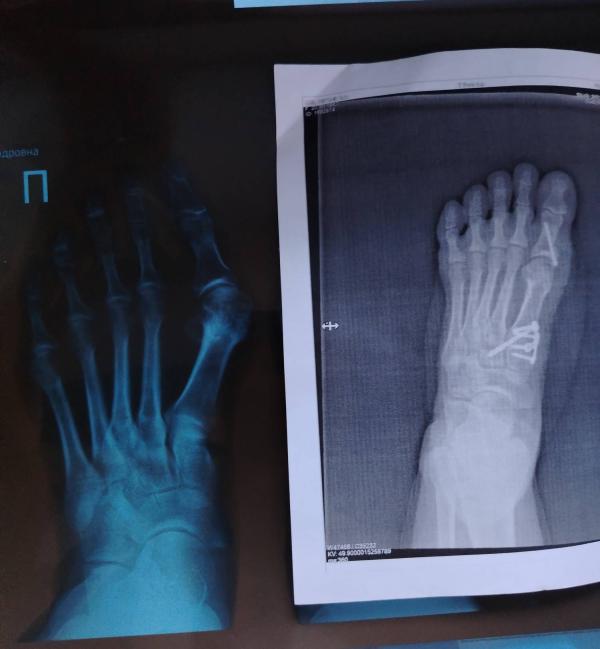

#халюсвальгус или в простонародье " косточка " на большом пальце. Вдруг кому нибудь пригодится.

Сначала в поликлинику к травматологу или хирургу. Он даёт направление в ниито (ниито имени Цивьяна) их там два (есть платно, есть бесплатно по квоте) вот по адресу Фрунзе 17 Д прийти с направлением из поликлинике, записаться на приём, там один врач по стопам. Он смотрит ваш рентген и говорит нужна ли вам операция. Если нужна, то он пишет спец документ, вы несёте его в поликлинику, сдаёте чуть чуть анализов и вам оформляют квоту. Ну и соответственно ждёте звонка. Моя очередь подошла через 2 года